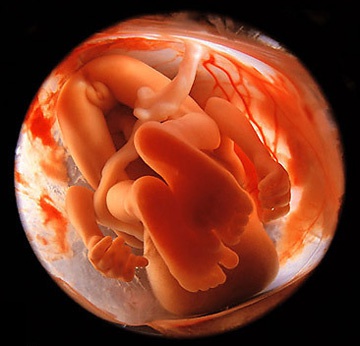

Плод активно растет и развивает навыки, готовясь к самостоятельной жизни. На 31 неделе продолжает развиваться мозг, увеличивается его размер, активизируются нервные окончания и формируются нервные связи. Нервные импульсы передаются быстрее, что способствует обучению. Органы и системы малыша развиваются, он может опорожнять мочевой пузырь и тренирует мочеиспускательную систему. Красные кровяные тельца теперь производит костный мозг.

Легкие малыша достаточно развиты, но не могут обеспечить самостоятельное дыхание. Малыш заглатывает амниотическую жидкость, которая обрабатывается и выводится в виде мочи. Капиллярная система функционирует, обеспечивая кровь кислородом для нормального кровообращения и развития мозга.

В организме плода накапливается жировая ткань, включая бурый жир, который располагается между лопатками, за грудиной, вдоль позвоночника и около почек. Бурый жир помогает новорожденному не замерзнуть, так как центр терморегуляции в головном мозге еще не развит. В течение первого года жизни бурый жир преобразуется в белый.

На 31 неделе ваш малыш, скорее всего, занял окончательное положение в утробе. Если он будет рожден головкой вперед, ягодицы сейчас направлены вверх. Внешний вид малыша стал более симпатичным: кожа уплотнилась, и кровеносные сосуды уже не просвечивают. Увеличивается количество подкожного жира, придающего округлые очертания. Ногти достигают кончиков пальцев.

На этом этапе черты лица становятся более четкими, нос и ушки формируются, шея удлиняется. Кожа малыша менее красная и сморщенная, под ней откладывается белая жировая ткань, придающая более натуральный цвет и способствующая разглаживанию кожи. Зрачки начинают реагировать на свет: во время бодрствования глаза открыты, во сне — закрыты. Цвет глаз у всех малышей голубой, а после рождения радужная оболочка накапливает пигменты, меняя цвет на серый, карий или зеленый.